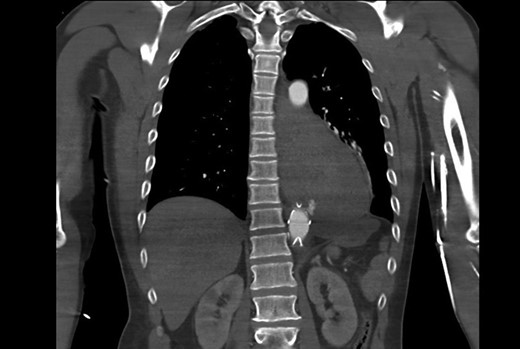

He re-presented with hypovolaemic shock and massive haematemesis four months later. A diagnosis of AEF was again confirmed on CTA (Fig. 2), just proximal to the previous aortic stent graft. He again had emergency percutaneous TEVAR covering the descending aorta from the level just below the left subclavian artery to just proximal to the celiac artery. Again, he was offered definitive surgery, but he was still not keen to have this at that time.

CT aortogram showing the extravasation of contrast from the aorta just proximal to the stent graft.